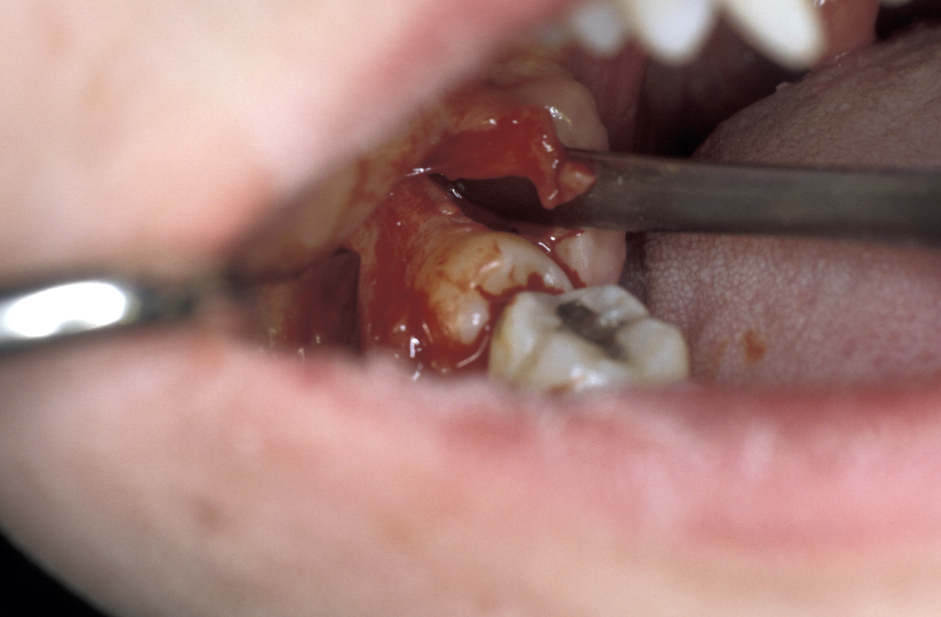

- Buccal Flap – a full thickness mucoperiosteal flap is raised from the buccal surface of the wisdom tooth area. The choice of incision varies, but commonly involves an incision along the external oblique ridge passing forward either around the second molar tooth or out into the buccal sulcus (Figure 3). If little or no bone is to be removed, a simple relieving incision may be all that is necessary. The important point is that dissection proceeds in a subperiosteal plane as this minimises postoperative swelling and trismus (Figure 4).

- Lingual Flap – some authorities do not raise a lingual flap at all. The popularity of this approach was from the days when accurate very high-speed surgical drills were not available and the ‘lingual split bone’ technique was popular in the UK and areas influenced by UK training. Their argument is that it is the process of actually raising the flap that causes injury to the lingual nerve. On the other hand, it is argued that the nerve is at risk from direct trauma from the burr/chisel if it is not retracted. Again, if used, the flap is raised by subperiosteal dissection. Here it is important not to ‘bow-string’ the nerve over the retractor (usually a Howarth’s elevator; Figure 1), but to widely undermine the lingual periosteum to allow the tissues to lie passively and use a wide subperiosteally placed retractor. The elevation of a small cuff of distal attached mucosa is designed for visibility, not for ‘lingual nerve protection’ and is not associated with an increase in morbidity (Figure 5).